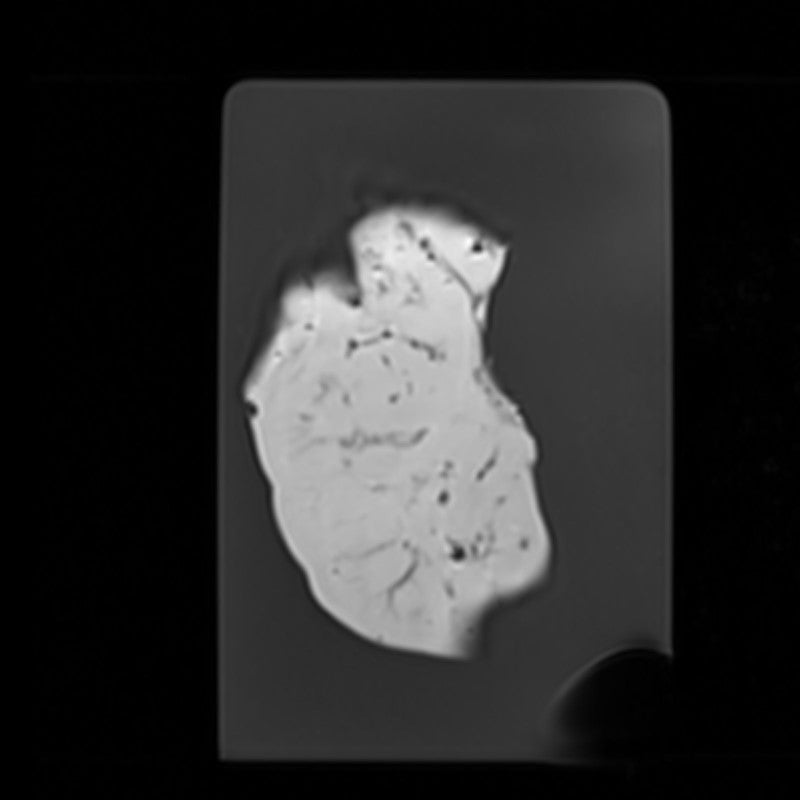

Kidney - Nephroblastoma